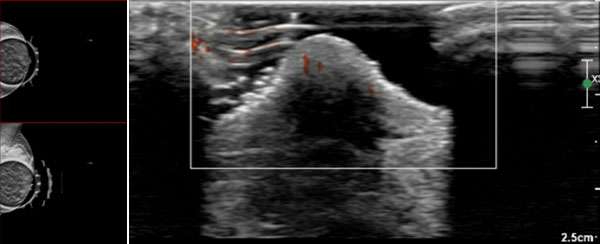

The mammographic findings of Paget’s disease include skin thickening in the nipple areolar complex region, nipple retraction, underlying suspicious calcifications, or a discrete mass. The ultrasound findings include nonspecific heterogeneity of the breast parenchyma, a mass, dilated ducts, and skin thickening or hypervascularity in the nipple areolar complex (Figure 3). Breast MRI may assist in further evaluation in the setting of negative mammogram and ultrasound findings (Figure 4).